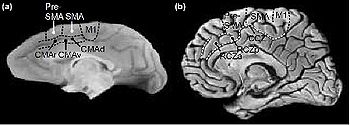

前帯状皮質(ぜんたいじょうひしつ、英: Anterior cingulate cortex ACC)は、帯状皮質の前部で、脳の左右の大脳半球間の神経信号を伝達する線維である脳梁を取り巻く"襟"のような形をした領域である。

この領域には背側部 (ブロードマンの脳地図における24野) と腹側部 (ブロードマンの脳地図における32野) が含まれている。前帯状皮質は血圧や心拍数の調節のような多くの自律的機能の他に、報酬予測、意思決定、共感や情動といった認知機能に関わっているとされている。

前帯状皮質はそれぞれの持つ機能に基づき、解剖学的に実行 (前側)、評価 (後側)、認知 (背側)、情動 (腹側) の4つの領域に分けられる。前帯状皮質は前頭前皮質と頭頂葉の他、運動系や前頭眼野とも接続して、刺激のトップダウンとボトムアップの処理や他の脳領域への適切な制御の割り当ての中心的役割を担っている。前帯状皮質は学習の初期や問題解決のような、実行に特別な努力を必要とする課題に特に関係していると考えられている 。エラー検出 (error detection)、課題の予測、動機付け、情動反応の調節といった機能を前帯状皮質によるものとする多くの研究がある。